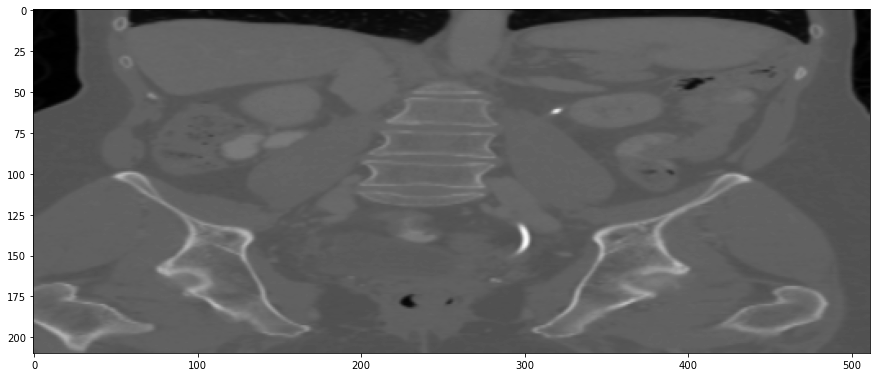

Refer to caption

(a) True Thick-slice image

(b) Simple Averaging

RMSE: 0.0250, PSNR: 38.0530

(c) Gaussian Averaging

RMSE: 0.1758, PSNR: 21.1182

(d) Direct Downsampling

RMSE: 0.0348, PSNR: 35.1697

(e) Proposed Simulation

RMSE: 0.0051, PSNR: 51.8504

Figure 3: Coronal-plane thick-slice image quality comparison across four simulation methods.